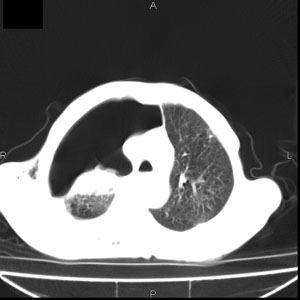

患者男,77岁,于3日前从树上摔下,头部查ct示蛛血,硬膜下出血,上腹部ct未见明显异常,右侧胸腔积液,左侧如常。肺部拍片示右侧肋骨多发骨折住院后今日来查肺部ct,我看到的是1。右侧胸腔血气胸并右肺上叶,中叶压缩性肺不张,2。右肺下叶肺挫伤并多发肋骨骨折,肌内及皮下积气3。左侧少量胸腔积液,我想请教的是3天前左侧胸腔里没有积液今天怎么出现了呢,是什么原因呢?请讨论。

有肺挫裂伤,有渗出,

1、外伤出血需要一定的时间

2、气胸存在时间长了,产生的胸膜渗液

支持楼主意见。外伤可有迟发性的改变。

考虑外伤性迟发性胸腔积液。

本人考虑有两种可能1)外伤迟发性的改变。

2)当时肋骨没有刺破肋间血管,可能这3天中由于运动导致